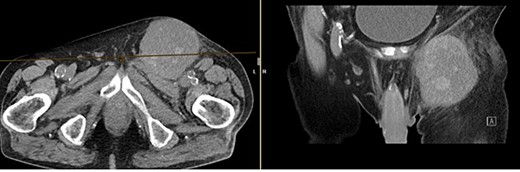

A month later, the patient presented again as the mass in the left groin area had increased in size. A CT (Fig 4) and another excision biopsy were performed. Histological examination revealed parts of a pleomorphic, most likely mesenchymally differentiated neoplasm. It was determined that the presence of a metastasis of the known prostate carcinoma could be ruled out. A myxofibrosarcoma was considered as a differential diagnosis, although the proliferation rate was rather low for this. Therefore, a reference pathology review was initiated.

CT of the abdomen from 26 July 2023: size-progressive metastasis in the left groin with infiltration of the adductor muscles; no dynamics in the primarily osteoplastic diffuse osseous metastasis.